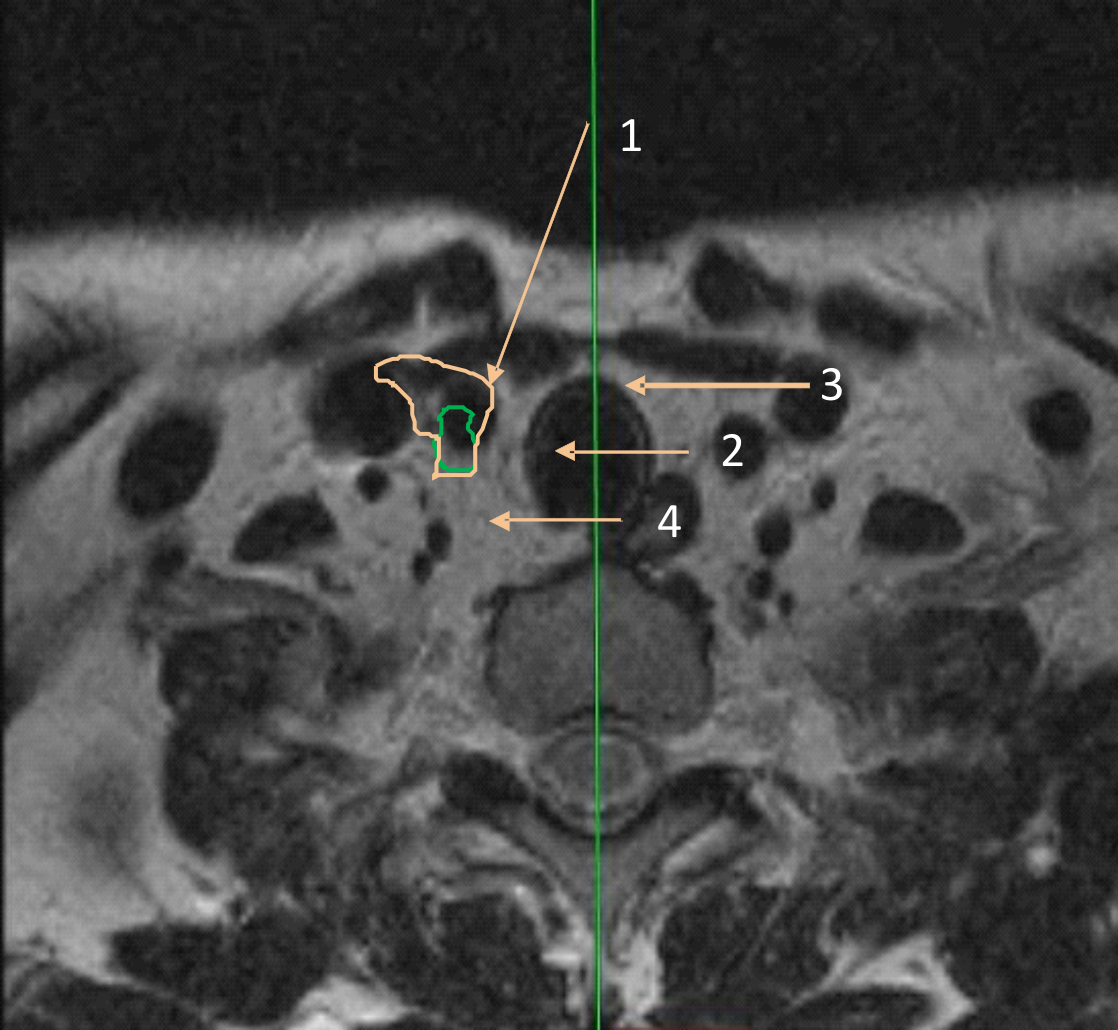

При втором типе щитовидная железа была интимно связана с короткими мышцами шеи, отмечалась диспозиция сосудистых пучков кзади и медиальнее. Пищевод при этом сохранял свою локацию (рис. 2).

Рис. 2. Заднемедиальный тип смещения. Плотный контакт левой доли щитовидной железы с короткими мышцам шеи; диспозиция сосудистых пучков кзади и медиальнее к срединной линии шеи: 1 – доля щитовидной железы; 2 – общая сонная артерия; 3 – внутренняя яремная вена; 4 – пищевод